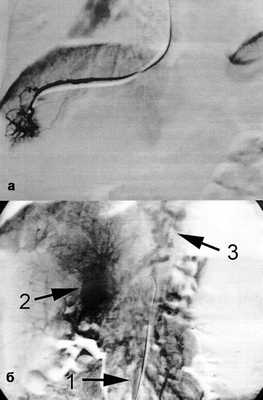

Уточнить уровень блока портального кровотока нам позволили такие исследования:

1) веногепатография - контрастное вещество, введенное посредством заклиненного в печеночной вене катетера, хорошо проходит через синусоидальное русло, что исключает синусоидальный блок портального кровотока (рис. 3); Рисунок 3. Веногепатограмма (а) и мезентерикопортограмма (б) перед операцией. 1 - верхняя брыжеечная вена; 2 - кавернозная трансформация воротной вены; 3 - варикозное расширение вен пищевода.

2) мезентерикопортография - визуализирована верхняя брыжеечная вена диаметром 8 мм, проходимая до места слияния с селезеночной веной, воротная вена кавернозно трансформирована, сброс контрастного вещества через вены пищевода (рис. 3, б);